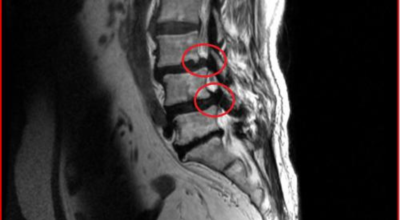

요추관 협착증은 척추 내 신경이 지나가는 통로가 좁아지는 현상으로 기인해서 신경이 눌리면서 이에 따른 여러가지 증상을 유발하는 질환을 의미해요.

허리 협착증은 척추관이 좁아지게 되면서 신경을 압박하게 되어 허리통증과 또한 다리에도 여러가지 증상을 일으키게 되는데, 발생 원인은 주로 노화로 인한 퇴행성 변화가 많았지만 요즈음는 옳지 않은 자세로 오랫동안 앉아있는 사람들이 많아지면서 생기는 경우도 많아졌으며, 선천적인 요인으로 나타나는 경우도 있답니다.

일상생활에서 허리 척추에 무리를 주는 행위가 반복적으로 행해질 경우 허리 뿐만 아니라 주변 근육과 인대의 퇴행이 빨라질 수 밖에 없어요. 허리 협착증의 경우 허리를 뒤로 젖히면 통증이 심하게 나타나지만 허리를 굽히면 척추관이 일시적으로 넓어지는 영향으로 통증이 줄기 때문에 자연스럽게 아프지 않은 자세를 하다보니 허리가 점점 굽는 자세를 만들 수 있어요.